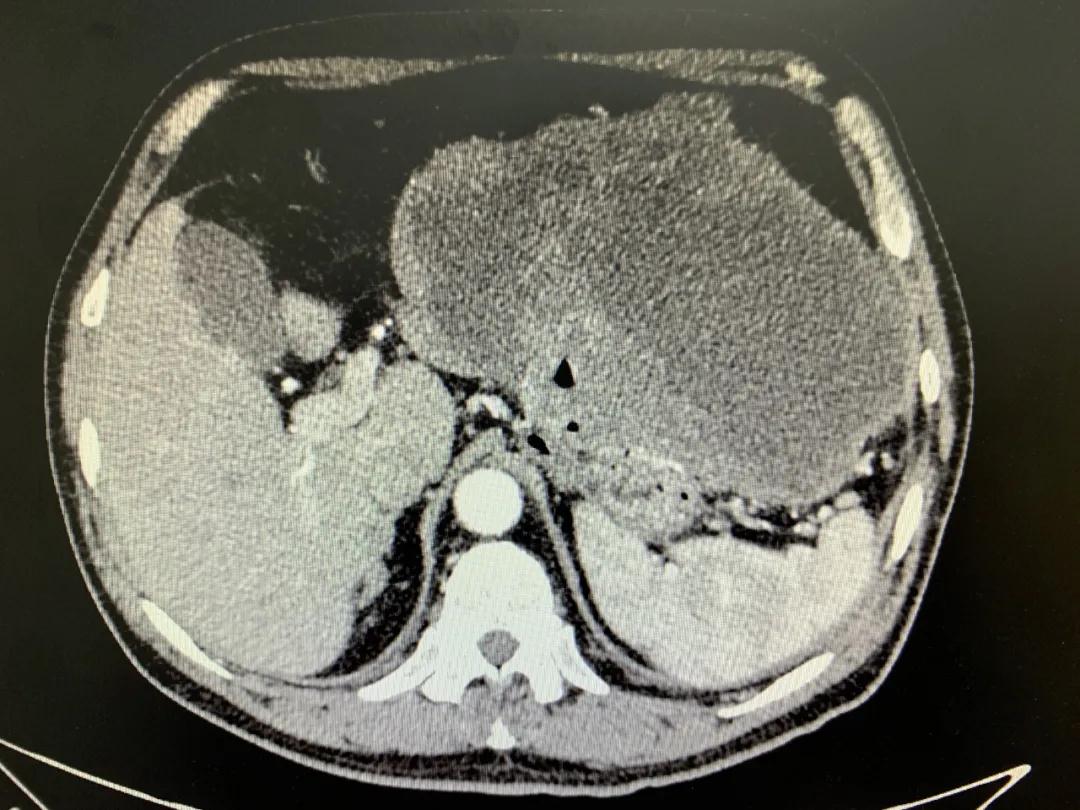

患者入院時(shí)血紅蛋白數(shù)值仍持續(xù)下降,出現(xiàn)失血性休克表現(xiàn),危及生命。消化外科二病區(qū)蔡磊主任接診后,組織科室迅速對患者進(jìn)行了全面的檢查。CT提示腫瘤大小約19.3*10.3cm,腫瘤內(nèi)提示大量積血。結(jié)合相關(guān)檢查,考慮為罕見的巨大胃間質(zhì)瘤合并出血。